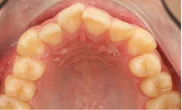

Обратилась с жалобой на скученность верхней и нижней челюсти средней степени тяжести — рецидив после подросткового лечения (ретейнер не носила).

КЛКТ, интраоральное сканирование, пародонтологическое обследование. Подвижности зубов нет, глубина зондирования — в пределах нормы.

Убыль кости — начальная, не превышает 1/4 длины корня.

рецессия десны в области нижних резцов, старые композитные пломбы на боковых зубах.

пародонтологическая подготовка (2 визита), профессиональная гигиена, установка Damon Clear на обе челюсти.

общий срок — 18 месяцев, 11 визитов для замены дуг и контроля. На 4-м месяце — видимое улучшение выравнивания. На 12-м — начат этап коррекции прикуса

с межчелюстными эластиками. На 18-м — снятие, установка ретейнеров.